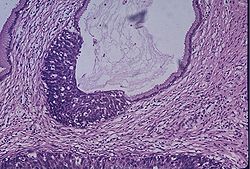

Neoplastik değişiklikler skuamokolumnar bileşkeden (junction) başlar. Serviks kanseri gelişmesinde serviks epitelinde birbiri ardısıra gelen değişiklikler olur, bu da serviks kanserinin erken tanısında önem taşır.

Bu değişiklikler sırasıyla:

1. Normal endoservikal kolumnar epitel

2. Skuamöz metaplazi

3. Hafif-orta-ağır displazi

4. Karsinoma in situ

5. Mikroinvazif karsinom

6. Belirgin invazif karsinom, şeklindedir.

Premalign lezyonların evrelendirilmesi

Preinvaziv servikal hastalık kavramı, 1947 senesinde invaziv kanser görünümüne sahip ancak epitelle sınırlanan epitelial değişiklikler tanımlandığında ortaya atılmıştır. Displazi ve CIS’ın (Karsinoma in situ) sürekli bir olayın farklı basamaklarını teşkil ettiğini düşünen Richart, 1967 yılında servikal intraepitelial neoplazi (CIN I, II, III) terimini tanımlamıştır. Sonraki çalışmalar bu lezyonların tedavi edilmemeleri halinde servikal kansere yol açabileceğini gösterdi. Şimdi ise tedavi edilmediği zaman erken CIN lezyonlarının çoğunun eş zamanlı olarak gerilediği bilinmektedir. Günümüzde anormal lezyonların gelişiminde premalign displastik değişikliklerin değerlendirilmesi için CIN sistemi kullanılmaktadır.

Servikal intraephitelial neoplazi (CIN):

* CIN I Hafif displazi (atipik hücreler epitelin alt 1/3’ünde sınırlı)

* CIN II Orta displazi (atipik hücreler epitelin alttan 2/3’lük kısmında ise)

* CIN III Ağır displazi (epitelin tamamına yakını tutulmuş ise)

* CIS Karsinoma in situ (epitelin tamamı tutulmuşsa)

Not I: CIN I düşük evreli skuamöz intraepitelyal lezyon; CIN II/III yüksek evreli skuamöz intraepitelyal lezyon olarak da isimlendirilir.

Not II: Bütün lezyonlarda bazal membran sağlamdır.

İnvaziv servikal kanserler genellikle uzun bir preinvaziv hastalık evresini izlerler. Mikroskopik olarak, invaziv karsinomlara ilerlemeden önce hücresel atipiden, değişen derecelerde servikal intraepitelyal neoplazilere (CIN) ilerleyen prekürsor lezyonlar spektrumu ile karakterizedir. CIN I lezyonlarının büyük çoğunluğunun geçici olduğu; kısa dönemlerde normale gerilediği veya yüksek derecelere ilerlemediği iyi bilinmektedir. Diğer taraftan, yüksek dereceli (CIN II, III)’ler, her ne kadar bu tür lezyonların da bir kısmı gerilese de, yüksek oranda invaziv kansere ilerleme olasılığı taşır. Servikal öncü lezyonların invaziv kansere ilerlemesinin ortalama 10 ila 20 yıl kadar uzun bir zaman aldığı bilinmektedir.